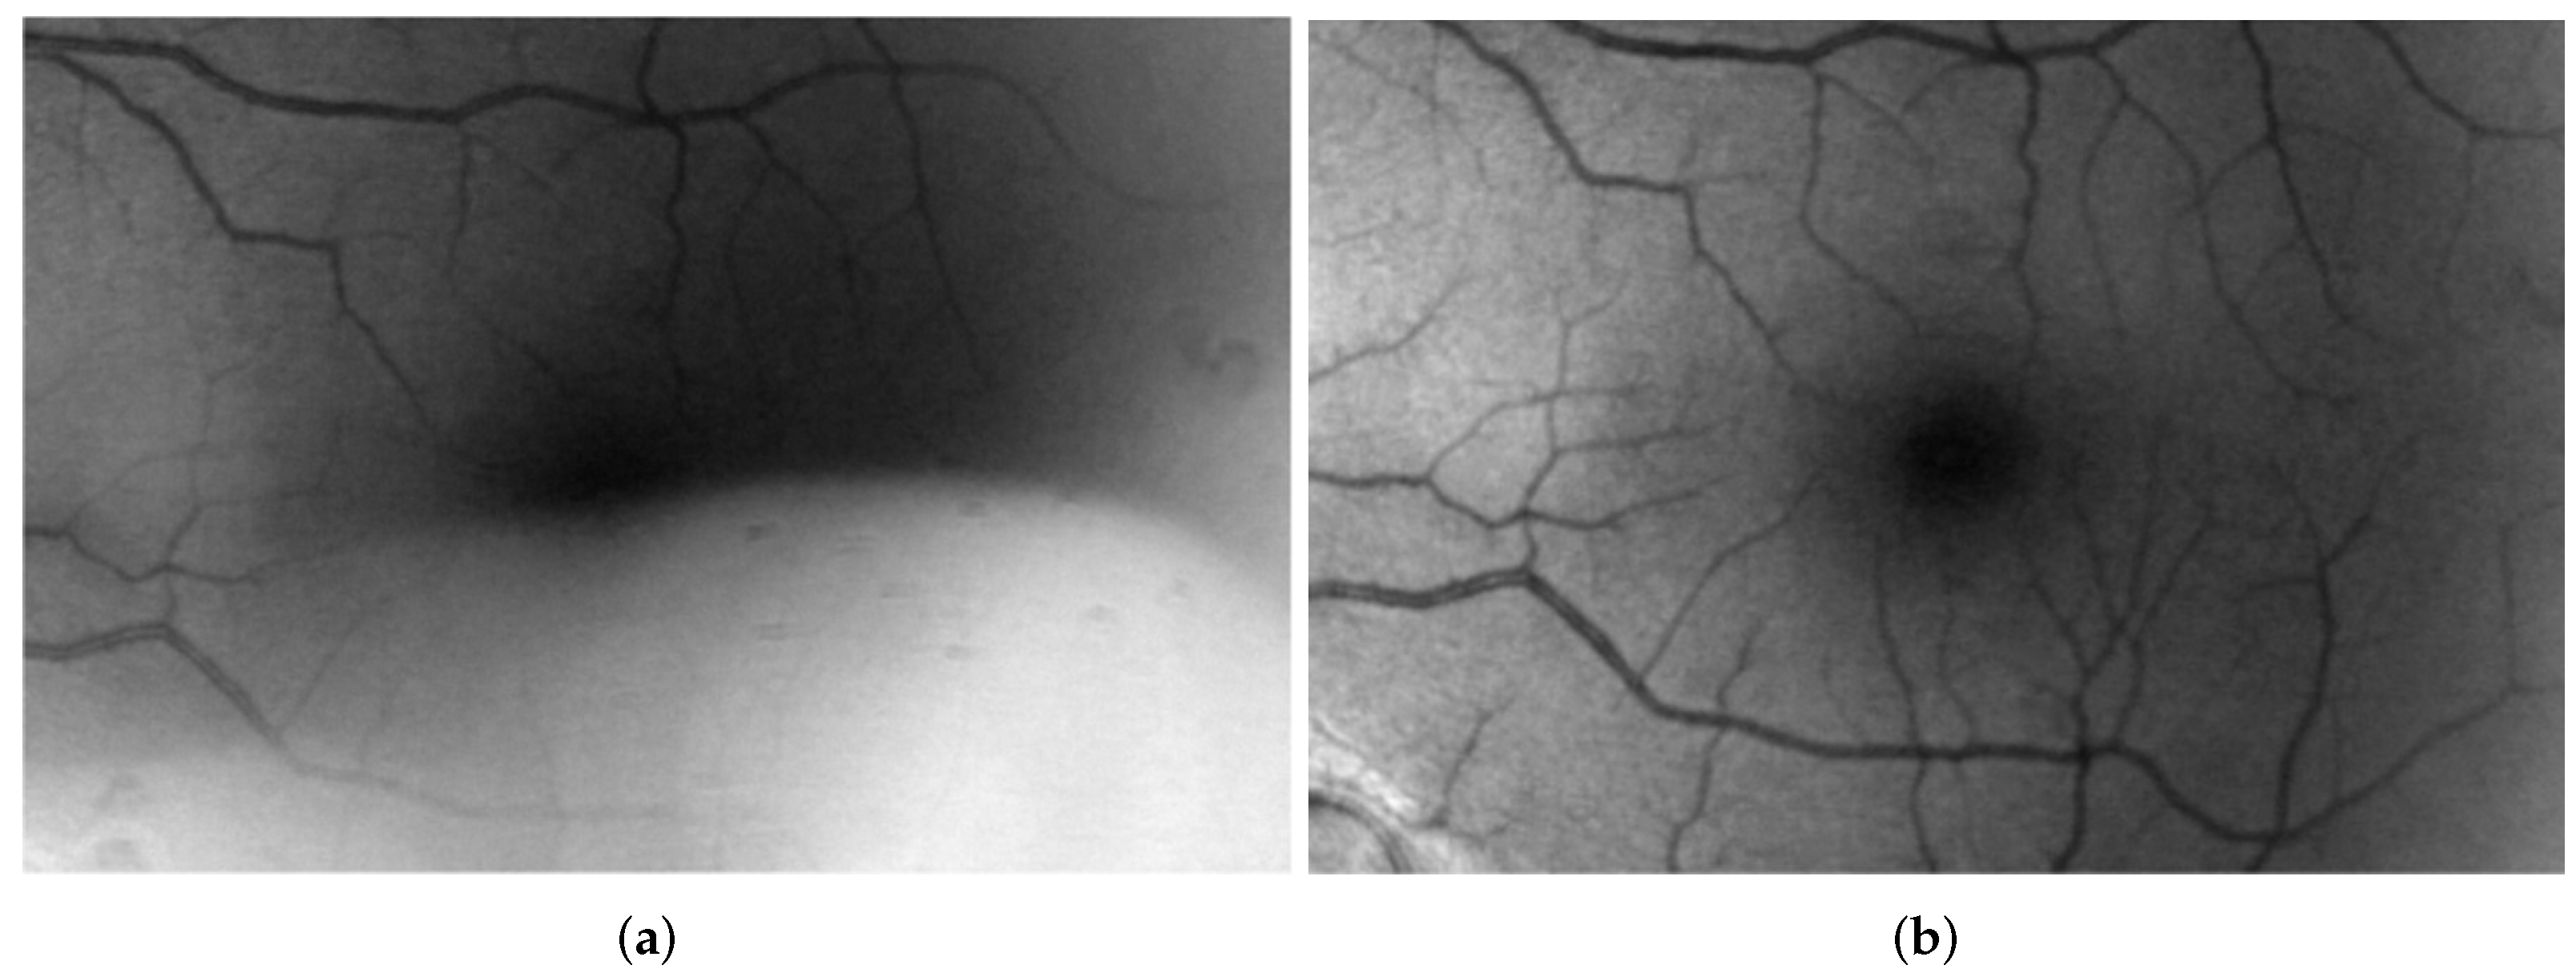

The McCann Retinex algorithm was used to normalize the contrast of the retinal fundus images and brain MRI. The effect of each iteration was observed, and the evaluation was based on the measurements of the PSNR and contrast. Figure 4 illustrates the effect of the iterative process of the McCann Retinex. On the left side (Figure 4a), the low quality image is observed. On the right (Figure 4b) is a high quality image from the HRF retinal image database. Figure 5 shows the output of the low (Figure 5a) and high quality images (Figure 5b) from the HRF retinal image database at each iteration from 1 to 20.

Figure 4.

(a) Low Quality Green Band Image from the HRF Retinal Image Database. (b) High Quality Green Band Image from the HRF Retinal Image Database.

Figure 4a shows a low quality retinal image from the HRF database that suffered from nonuniform contrast that affected the visualization of blood vessel detail. The iterative McCann Retinex algorithm was used, and each iteration affected the image quality and obtained more details of the image. After each iteration, the PSNR and PSNR improvement and contrast were measured. The low quality green band image from the HRF database had a PSNR of 37.22 dB, and it improved up to 3 dB from iteration 1 to 20 (Figure 6a,b); similarly, the contrast increased from 20.9 at iteration 1 to 34.12 at iteration 20 (Figure 6c. The high quality green band image from the HRF database had a PSNR of 39.12 dB, and it improved up to 3.74 dB from iteration 1 to 20 (Figure 6d,e); similarly, the contrast increased from 40.1 at iteration 1 to 51.1 at iteration 20 (Figure 6f). This improvement on high quality HRF images allows better observation of the retinal vessels and retinal abnormalities and also impacts the performance of the segmentation process.